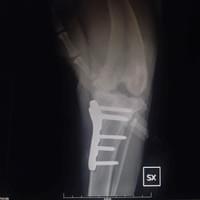

Chirurgia ortopedica

Nella nostra struttura si offre un servizio di chirurgia ortopedica tramite l’utilizzo di diverse tecniche operatorie, quali i fissatori esterni e l’utilizzo di placche e viti (fissazione interna), per il trattamento delle fratture .Per il trattamento della Rottura del legamento crociato craniale del ginocchio, si effettuano le metodiche piu’ moderne come: la TTA POROSA (tibial tuberosity advancement) e la TPLO (osteotomia livellante del piatto tibiale) .

Ci occupiamo anche delle patologie chirurgiche legate alla Displasia di rotula.